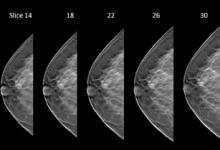

AI is also helping simplify complex tasks and help reduce the reading time on involved exams. One example of this is in 3-D breast tomosythesis with hundreds of images, which is rapidly replacing 2-D mammography, which only produces 4 images. Another example is automated image reconstruction algorithms to significantly reduce manual work. AI also is now being integrated directly into several vendors' imaging systems to speed workflow and improve image quality.